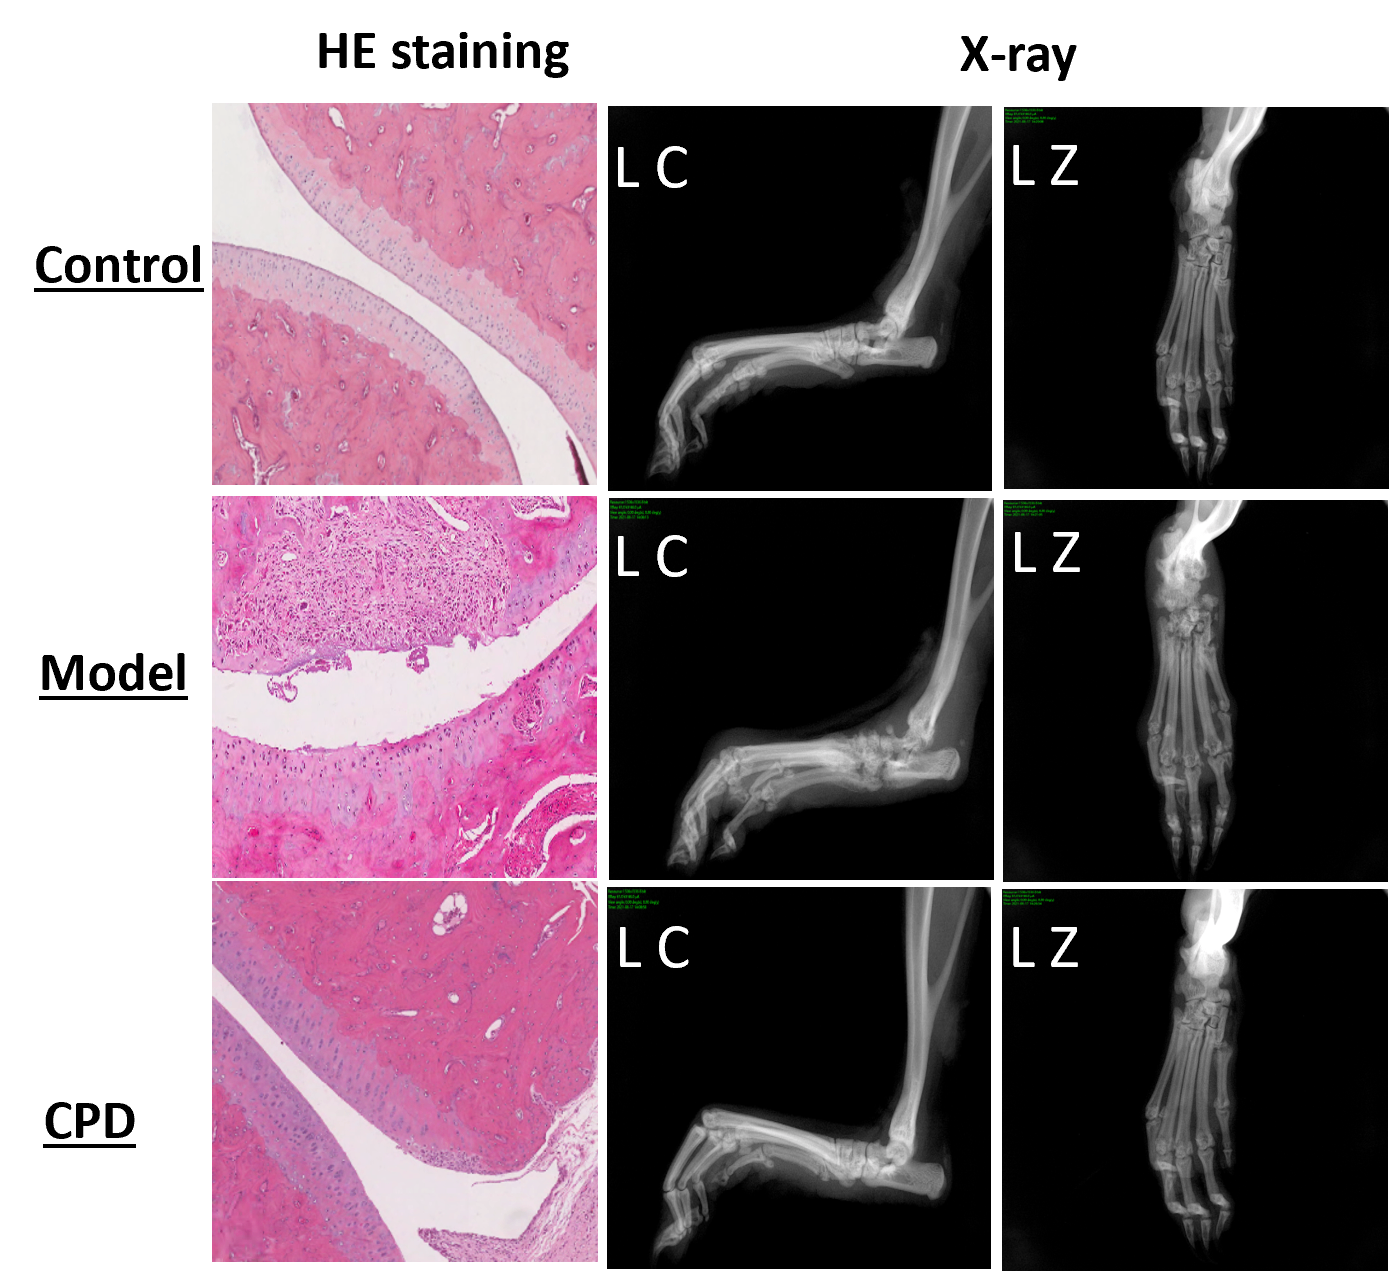

The model changes are also observable directly during the anatomical and histopathological evaluation below (CPD = tofacitinib).

Model application for compound testing